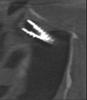

Мистер Зуб Опубликовано 1 мая, 2013 Поделиться Опубликовано 1 мая, 2013 Здравствуйте! установка имплантов для меня закончилась тем, что один из трех "ушел" в гайморову пазуху. Причем "ушел" полностью, и находится в данное время около переносицы. Размер импланта 11*4,5 мм. Теперь этот шуруп живет в моей голове своей жизнью:меняет положение, переворачивается (это видно на снимках). Хирург, который это допустил говорит мне, что ничего страшного, обрастет слизистой и пусть остается там, а мне поставят другой имплант. Консультации с лорами категоричны - нужно убирать, причем операция может быть довольно травматичной. Вопрос: что делать? как жить с шурупом в голове и чем это грозит? Какие могут быть варианты его извлечения? К каким специалистам обращаться по поводу операции? К лору или к челюстно-лицевому хирургу? Ссылка на комментарий

Bier Опубликовано 1 мая, 2013 Поделиться Опубликовано 1 мая, 2013 Сделал отверстие в верхней челюсти и достал. Имплантат довольно большой, его видно в пазухе. З.ы. Мжет вы меня не так поняли, я врач, доставал у пациента мною поставленный имплантат, который мигрировал в пазуху. 2 Ссылка на комментарий

Bier Опубликовано 2 мая, 2013 Поделиться Опубликовано 2 мая, 2013 Через лунку не удалить, не реально. Надо вскрывать переднюю или латеральные стенки пазухи и удалять. Кстати, ЛОР эндоскопист сделает тоже самое. Имплантат через естественное соустье все равно не достанешь. 2 Ссылка на комментарий

Мистер Зуб Опубликовано 8 мая, 2013 Автор Поделиться Опубликовано 8 мая, 2013 Насколько травмотична такая операция?Какие последствия? Сроки восстановления? сравнима с операцией синуслифтинг. За неделю заживет. Поздравьте меня сегодня была операция . Лор хирург досталимплант через соустье . Болевые ощущения на допустимо - терпимом уровне. Я уже дома крови нет никаких последствий не ощущаю.На операции присутствовал мой стоматолог записывали операцию на видео. Надо будет посмотреть))).Всем спасибо за участие!С днем ПОБЕДЫ !! 1 Ссылка на комментарий